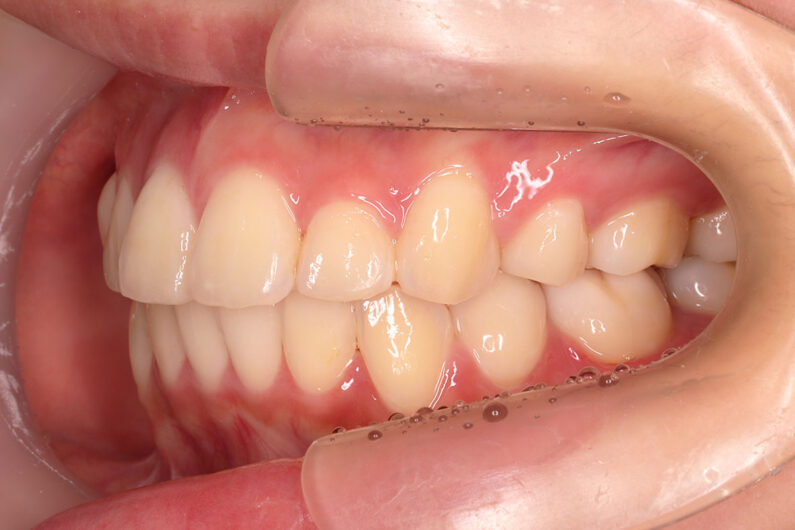

他院から紹介の患者さんです。 前歯、下の歯のガタツキをきれいにしたいということで治療を決断されました。

上顎前歯6mm、下顎前歯2.5mmの前突の状態で、口唇も前突しています。 小臼歯抜歯したスペースを使い、叢生(がたつき)と前突した前歯の後退を目標にしました。 この方も希望により、アンカースクリューは使用せず、通常の顎間ゴムで対処してもらいました。

マルチブラケット 動的治療期間 3年5か月 調整回数29回

治療後は前歯は後退し、前歯の傾斜度も良くなっています。 口唇の緊張感も改善し、エステティックラインも綺麗になりました。